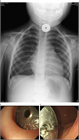

1. CTは、異物の描出のみならず、縦隔気腫、穿孔、腸閉塞など合併する重篤な病態の評価にも有用であり、可能であればCTの施行が望ましい(推奨度2)